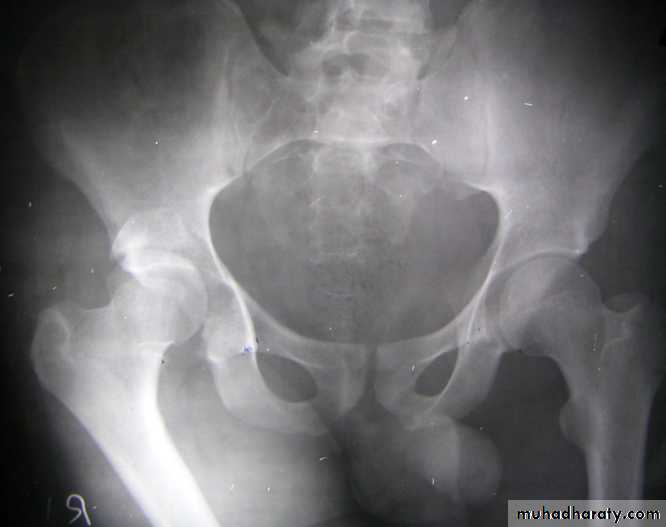

Posterior dislocation:

Mechanism of injure:4 out of 5 traumatic hip dislocations are posterior.

Usually occur in road traffic accident when the knee striking the dashboard

the femoral head is forced out of its socket sometimes associated with fracture.

The golden role is to x ray the pelvis in every case of sever injure

and with femoral fracture to include both the hip and knee.Radiological examinations

X-R AP view we can see the dislocation with or without associated fracture posterior wall of the acetabulum,or fracture head of the femur,

And neck of femur.